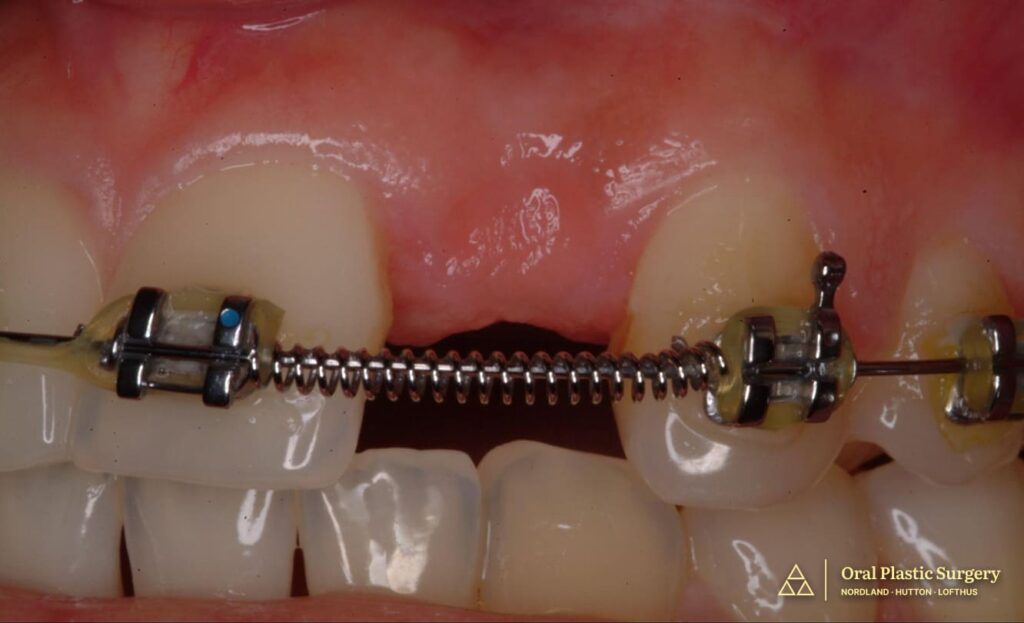

Active orthodontic treatment establishes ideal spacing and root angulation of adjacent teeth. Coordination between orthodontist and periodontist ensures optimal three-dimensional positioning for future implant placement.